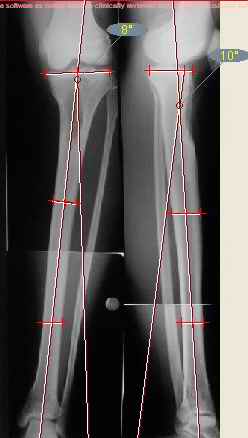

Продолжение обсуждения, начатого в октябре прошлого года (см. здесь) Наконец-то оперировали эту пациентку. Биопсию сделали - опухолевого ничего нет. Пока все участвовавшие в обследовании смежные специалисты и ортопеды сошлись, что это молокальная монооссальная фиброзная дисплазия. 20 марта наложили аппарат, сделали чрескожную остеотомию. К 3 апреля все докрутили. Сегодня заштифтовали. Начальные и итоговые снимки в приложении. Рекурвацию можно было еще немного больше устранить, и чуть кзади сместить диафиз. Но вроде и так ничего выглядит, по сравнению с тем, что было. Комментарии приветствуются.